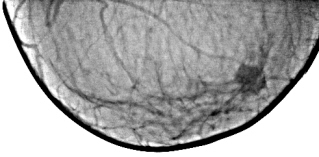

Признаки, представленные в таблице № 2 – иллюстрации 1, 2, 3, 4. (№ 1 – снимок в прямой проекции, № 2 – фрагмент с «патологическим образованием», выделенный навигатором, № 3 – снимок в боковой проекции, № 4 - фрагмент с «патологическим образованием», выделенный навигатором).

В верхнем наружном квадранте правой молочной железы, в передних отделах регистрируется тень узлового (опухолевого) образования неправильно округлой формы, с неровными, нечеткими контурами, с радиарной тяжистостью в «окружающую ткань», неоднородной структуры, с мелкими эксцентрическими просветлениями и очаговыми уплотнениями. При значительном увеличении изображения также на фоне «узла» определяются мелкие уплотнения.